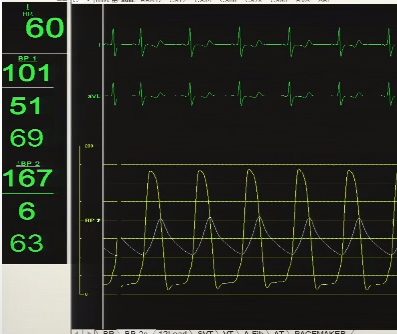

术前平均跨瓣压差66mmHg

术前超声提示左室最大射血速度4.6m/s

瓣膜释放过程稳、准、快,释放后定位可,形态佳,工作正常,平均压差6mmHg

术后即时数据显示,患者平均跨瓣压差降至6 mmHg,AV前向血流速度降低至1.7 m/s,手术效果非常理想。